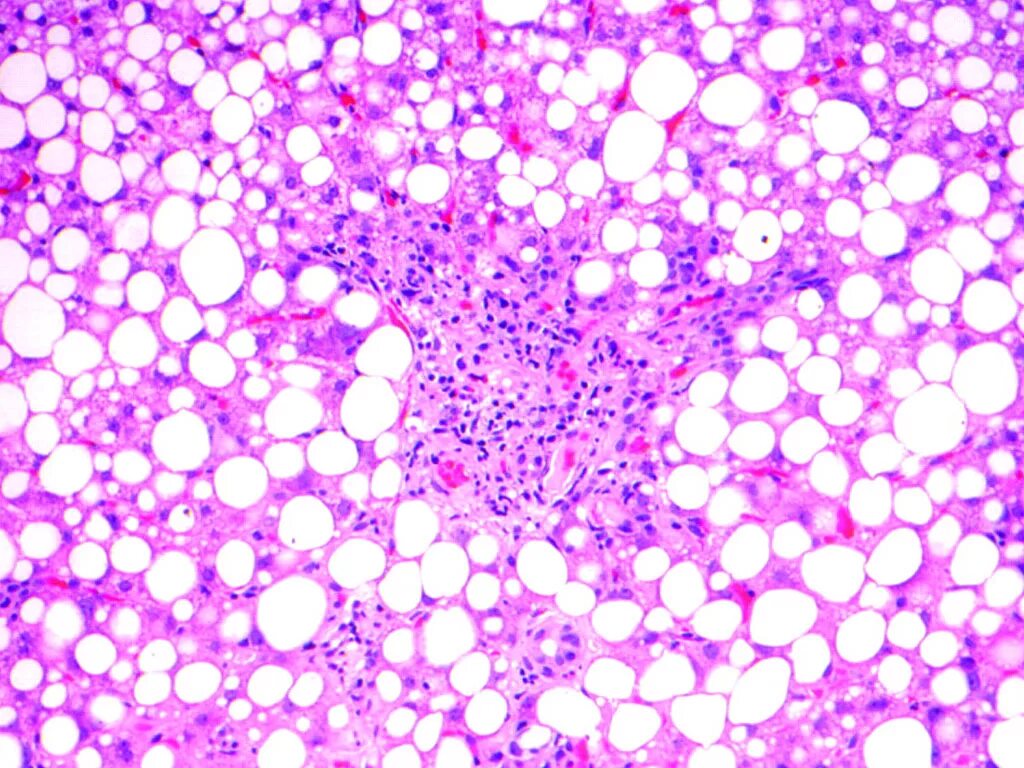

Стеатоз печени патанатомия. Жировая дистрофия печени гистология. Жировая дистрофия печени микропрепарат. Жировой гепатоз препарат патанатомия. Стеатоз 3.

Жировая дистрофия печени судан 3 гематоксилин. Неалкогольный стеатогепатит гистология. Жировая дистрофия печени патологическая анатомия. Стеатоз 3. Жировой гепатоз (стеатоз) печени.

Стеатоз печени гистология. Степень стеатоза печени s3. Острый жировой гепатоз препарат. Стеатоз печени микропрепарат судан. Стеатоз 3.

Стадии стеатоза печени s3. Жировая дистрофия печени микропрепарат. Стеатоз печени дистрофия. Жировой гепатоз гистология. Макропрепарат: жировая дистрофия печени гепатоз.